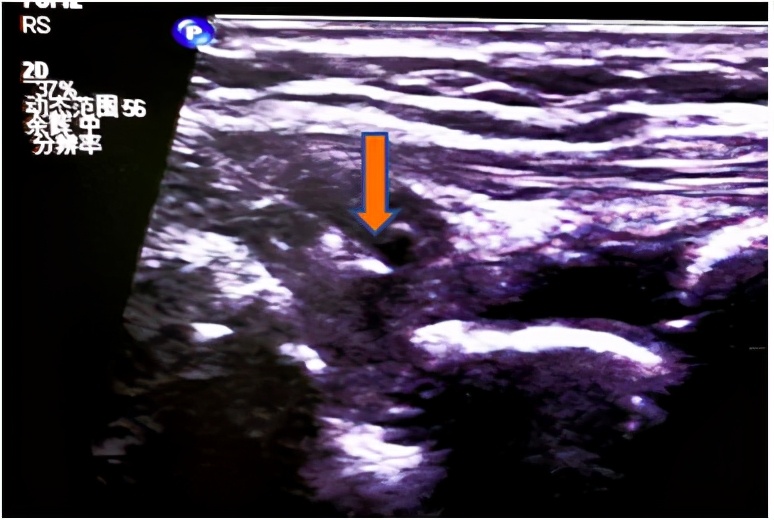

图二超声引导下注射治疗,箭头所示为针尖。

经过一番检查,超声发现手、腕部肿痛处存在明显滑膜炎,血流丰富,并且腕骨表面已经出现了侵蚀表现。最终结合化验结果、症状查体及超声检查结果,患者被诊断为 类风湿关节炎 ,给予相应的药物治疗后,肿痛有缓解,但仍有反复,于是再次复查腕关节超声,腕关节背侧滑膜炎较前好转,但仍较严重。胡安鑫副主任医师和其主治医师沟通后,征得患者同意,决定行 超声引导下腕关节注射治疗,直接将药液注射至滑膜炎最严重处 ,不久患者症状便得到了逐渐的缓解。